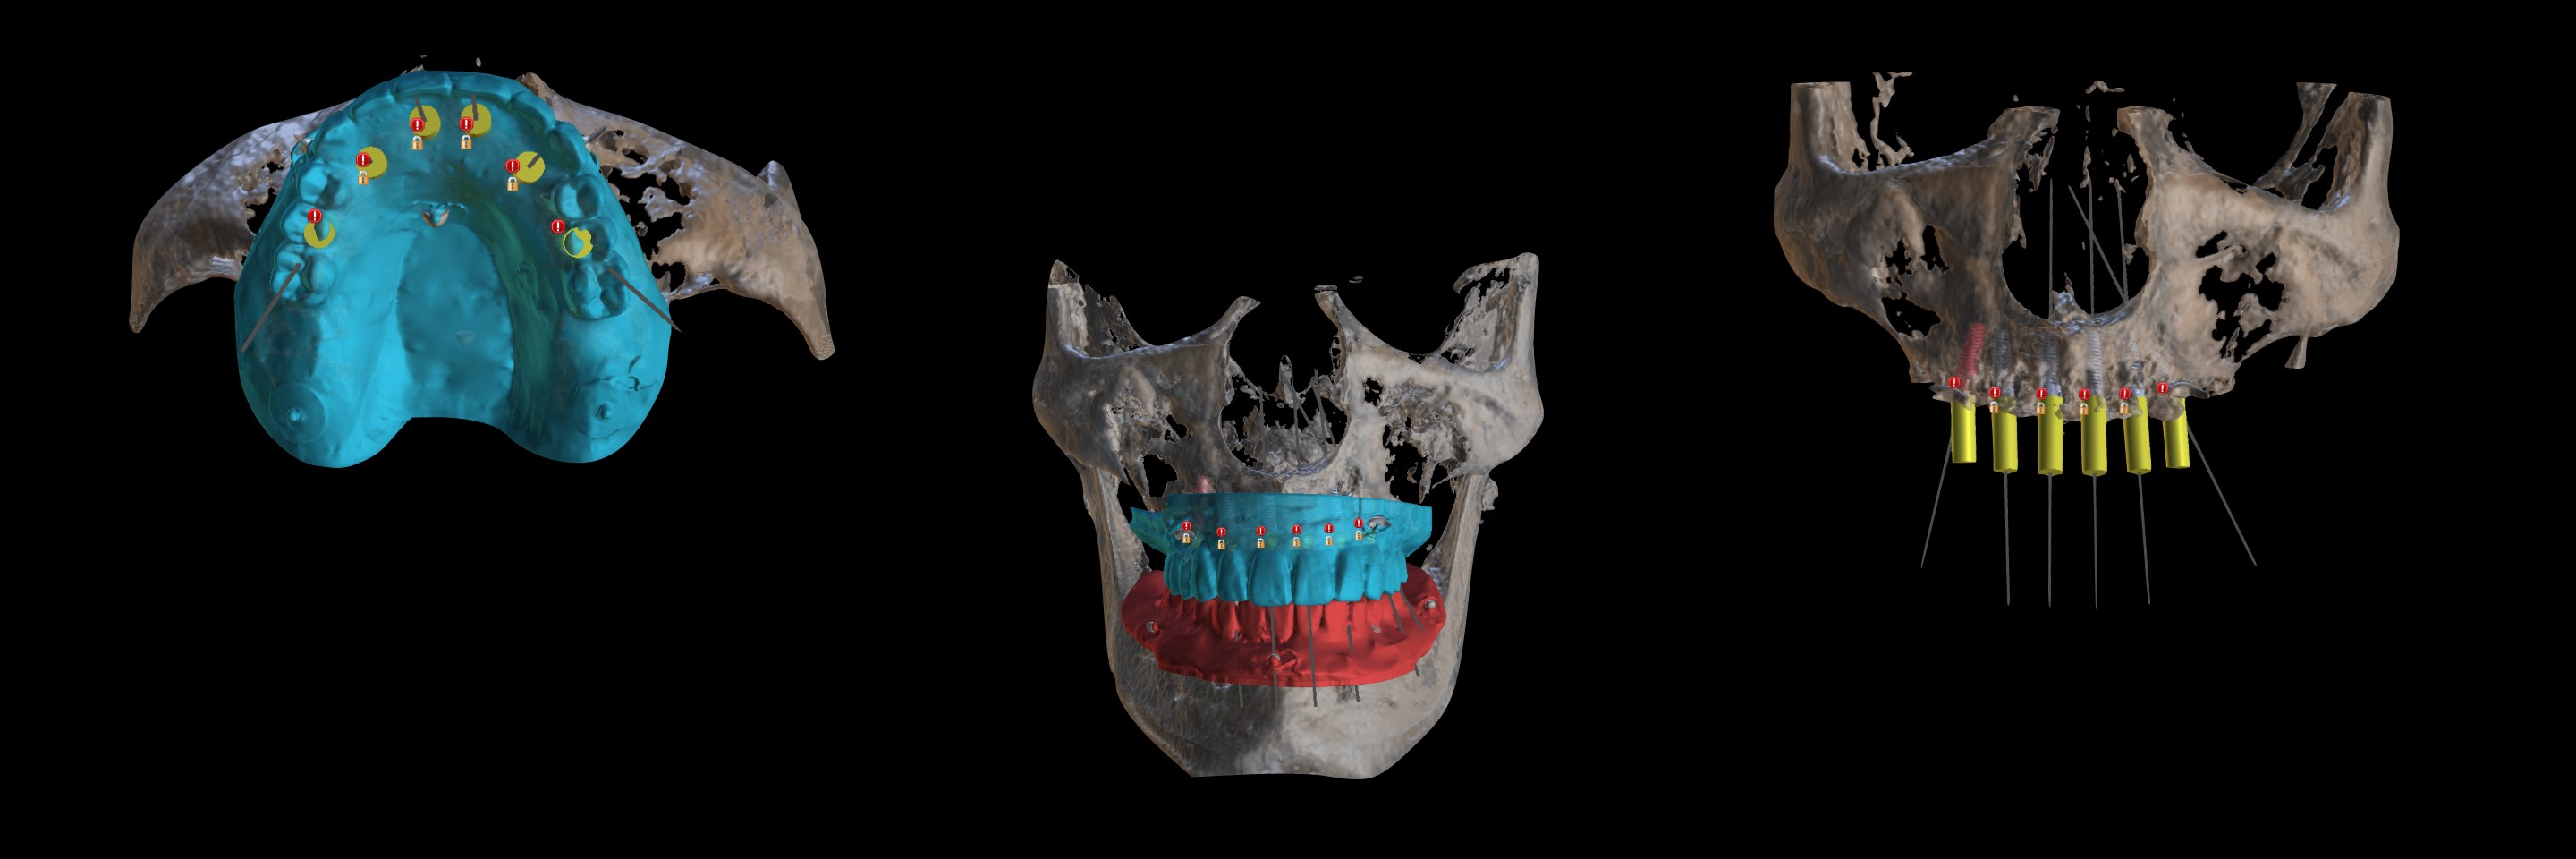

• Virtual implant placement for All-on-X case

• Digital surgical guide design and fabrication

• To make a virtual implant placement for All-on-X Clinical case

• Virtual implant placement for All-on-X case

• Digital surgical guide design and fabrication

Director’s Clinical Cases

Director’s Clinical Cases